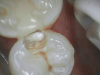

Figure 1 shows a pretreatment photograph of a tooth No. 20. In Figure 2, the circled area of the x-ray indicates the interproximal area where the clinician was uncertain if caries was present. Though x-rays are useful, transillumination is more sensitive and optimal for detecting caries in the early stages.12 With new devices, clinicians can acquire more information before working on the tooth. As shown in Figure 3, caries was confirmed using the transillumination system (CariVu), though it did not show up on an x-ray. The clinician was able to show the image to the patient. The open-tooth camera image then revealed the extent of the caries in the exact position that was displayed in the transillumination image (Figure 4). This is a significant advantage in minimizing preparations and saving valuable tooth structure.

Fig 3. Caries confirmed through use of transillumination.

Figure 3